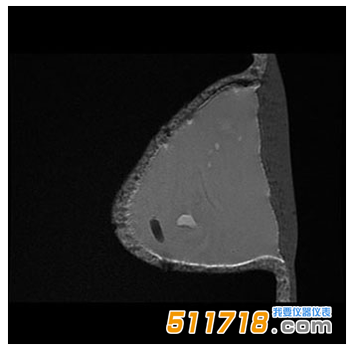

CIRS 073多模式乳房活檢和超聲波訓練模體 MR T1 SE